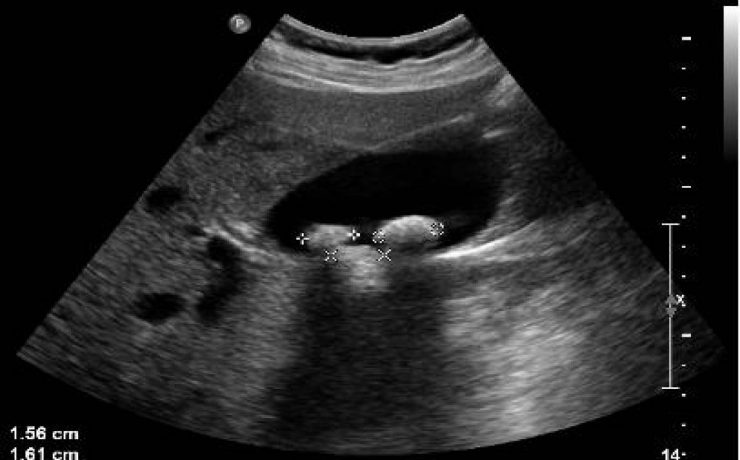

Hiperplasia prostática benigna

La hiperplasia prostática benigna (HPB) es muy prevalente en atención primaria; es el principal motivo de consulta por problemas urológicos en el hombre y es el primer diagnóstico que debemos pensar ante un paciente mayor de 50 años que consulta por síntomas obstructivos y/o irritativos. El diagnóstico de HPB es